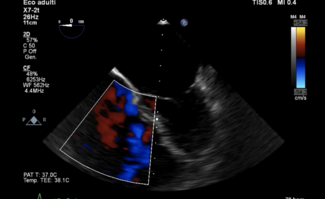

J.M. Montero-Cabezas, MD;  V. Delgado, MD, PhD;  F. van der Kley, MD

High rates of spontaneous rupture and death have been described when the pseudoaneurysm is left untreated. In this case, transthoracic echocardiography allowed optimal characterization of the defect and successful procedure guidance, avoiding...